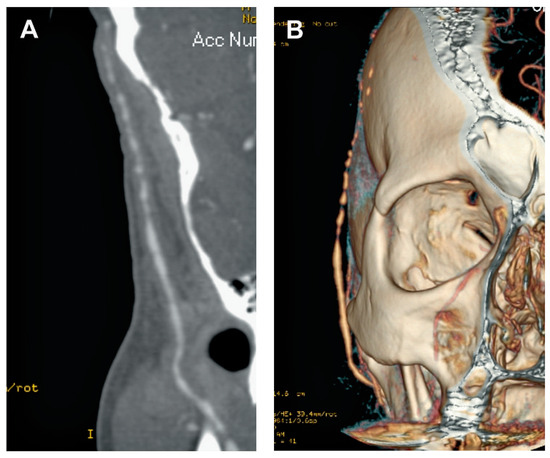

Summary. We report two cases of a 83- and a 78-year-old female with tetralogy of Fallot (TOF) who underwent operation at an advanced age in their 30’s, making them the oldest patients repaired for tetralogy of Fallot [...]